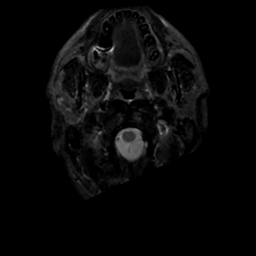

MR Study #3, February 24, 1991 -- Slice #1

[Home][Help][Clinical][Tour 1][Tour 2] Slice 1